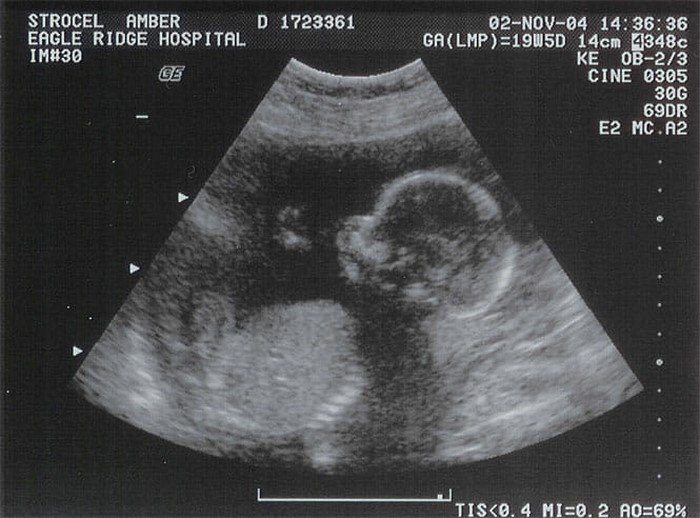

На 21-й неделе, после УЗИ, супруги узнали, что ждут девочку. Бриони с Марком решили назвать малышку Ава Грейс. Будущие родители даже не представляли себе, что вскоре их счастье обернется кошмаром!

Шла 30-я неделя беременности, когда Бриони заподозрила неладное. Малышка в ее животе, которая раньше была такой активной, совершенно перестала двигаться. Быстро посовещавшись, Кервуды опрометью бросились в больницу за профессиональной помощью.

Как выяснилось, Ава Грейс отчего-то перестала расти на 22-й неделе беременности. Оставлять малышку в животе матери дальше означало бы убить младенца.